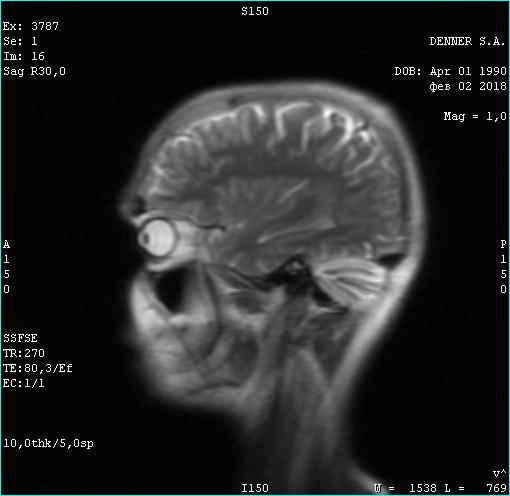

Фома неверующий. Вот этого парня я сейчас лечу. Опухоль за 3 месяца лечения уже не активна. Частично пошло ее разложение. Тремор сердца исчез. Походка восстановилась. В августе скину новое мрт с результатом лечения. Динамика на снимке. Ядро опухоли гибнет за 3 месяца. Господа!!!! За 3 месяца!

Тип файла: jpeg 02.02.2018.jpeg (22.5 Кб, 732 просмотров)

Вверху февраль 2018. Внизу май 2018

Опухоль контраст не накапливает. Связи с костью уже не имеет. Головка опухоли начала разлагаться. Врачи в шоке. А я злорадствую. Сергей мне поверил и сейчас копает огород на Алтае, хотя должен был умереть в июле. Моя карма получила жирный плюс...

Фото мрт сделаны немного в разных ракурсах, (зачем, непонятно-наверное чтобы не признавать эффект оздоровления ), но положительная динамика все равно видна. И пациент начал жить полноценной жизнью - секс, загар, копание огородов и рыбалка...